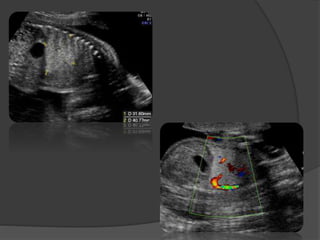

Diagnostic anténatal

 Dés la 19e SA par échographie

 Images hyper-échogènes circonscrites

homogènes volontiers arrondies dans la

SIL et triangulaires dans la SEL

 Doppler: vaisseau systémique

 Recherche de malformations associées